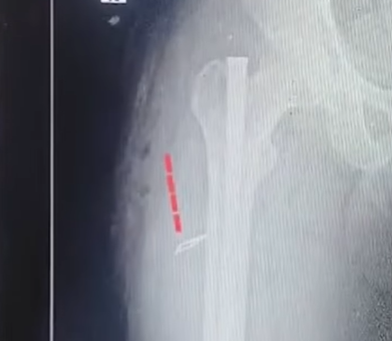

Kakinada Ortho Surgeon, Nurse Suspended After Blade Left Inside Patient

Health minister Satyakumar Yadav ordered an immediate inquiry, expressing strong displeasure over the incident